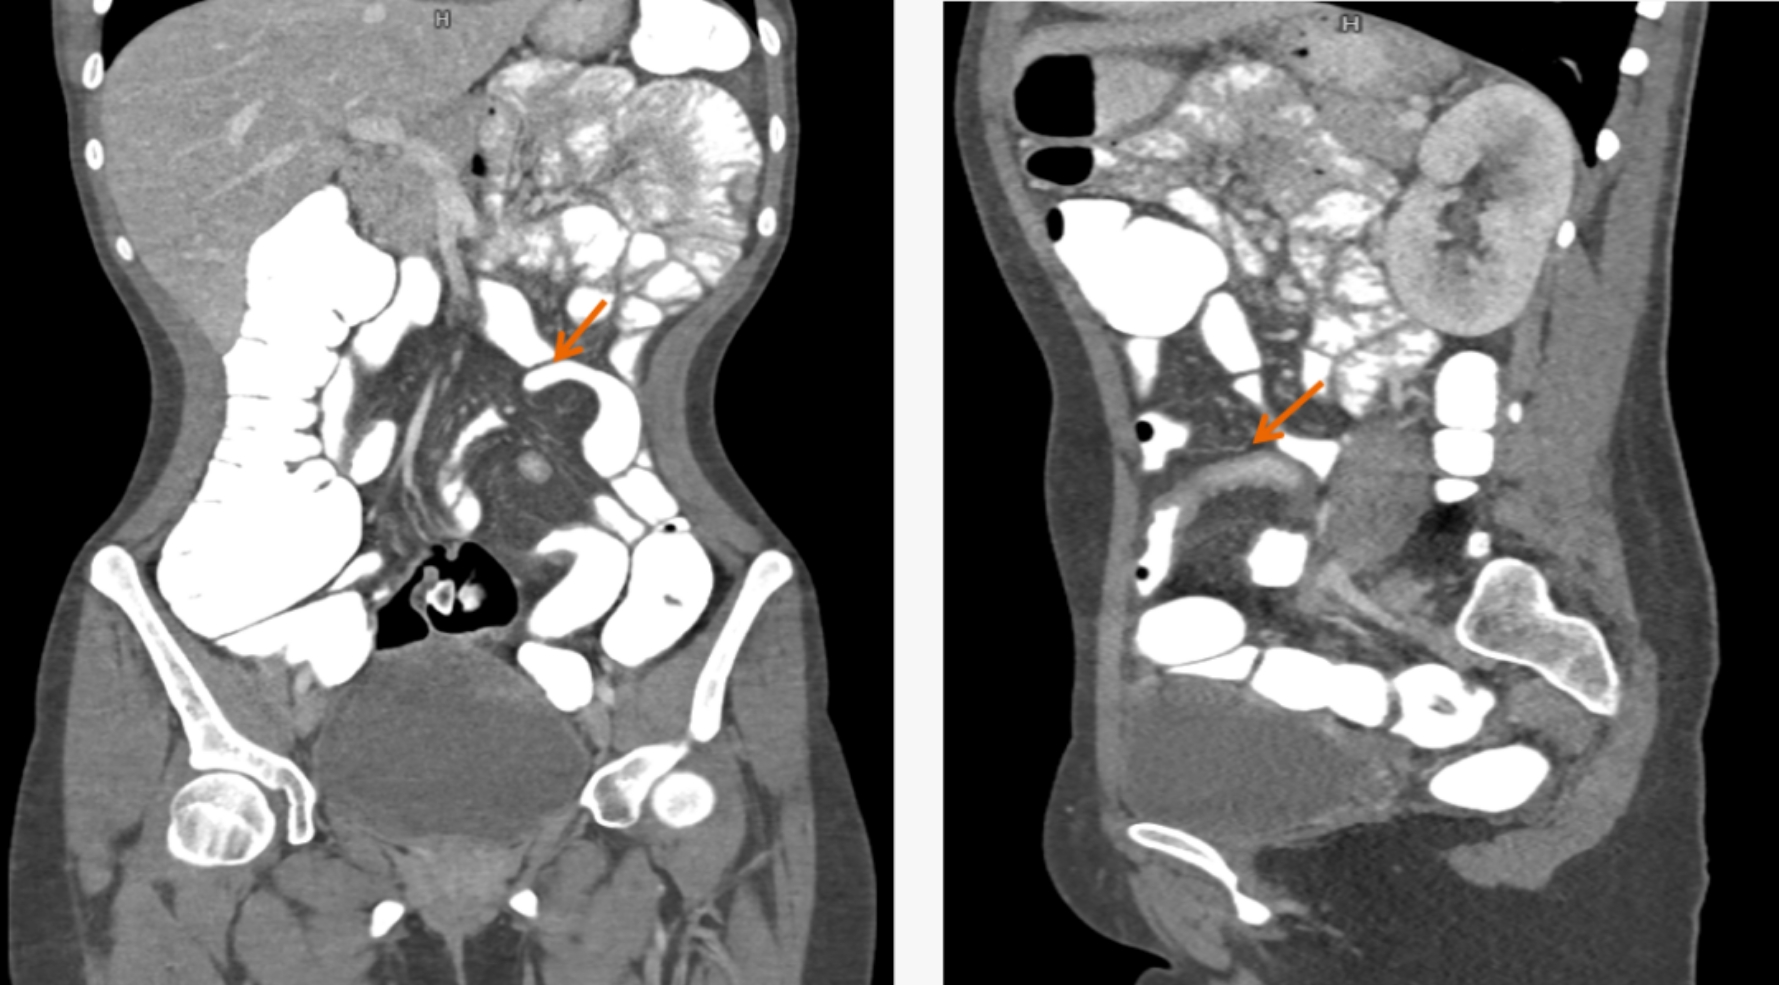

該設(shè)備,可以在短時(shí)間完成對(duì)冠狀動(dòng)脈缺血、肺栓塞、主動(dòng)脈瘤的一站式檢查,也可在在短時(shí)間完成對(duì)頭部血管、頸部血管、腦實(shí)質(zhì)血液灌注的一站式檢查,為腦卒中和急性胸痛患者的早期診斷和治療能力贏得黃金時(shí)間。